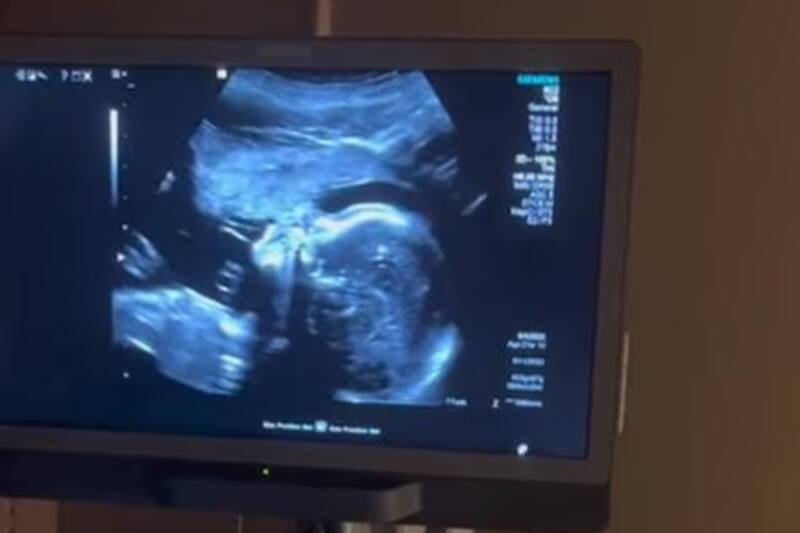

Sorprendente video se hizo viral en redes sociales, ha sido protagonizado por una mujer embarazada y el bebé que lleva en su vientre al demostrar la inmensa conexión que existe entre una madre y su hijo, estando en un ultrasonido.

A través de un TikTok se compartieron imágenes de este caso que ha dado la vuelta al mundo por la ternura que provocó en miles de usuarios. En el video se observa a una madre cantando mientras hacen un ultrasonido y el feto al escuchar la melodiosa voz de su madre también gesticula como si cantara.

La usuaria @damaris_samples_oficial, compartió el video y se observa como la madre está recostada en la camilla mientras la ecografía hace su trabajo y enfoca con la maquina al pequeño. De pronto, quien sería el padre del bebé le pide a la mujer que cante “Aleluya” de Leonard Cohen.

Ella no duda en realizar la interpretación de la canción e inmediatamente se logra ver como el bebé mueve su boca como si estuviera cantando junto a su mamá. Todos en la sala quedaron sorprendidos por el particular suceso. Ahora el video suma más de 2.1 millones de reproducciones, 273 mil likes y miles de comentarios.